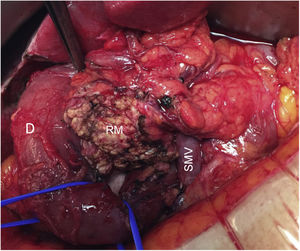

In all cases, intraoperative prophylactic antibiotic therapy was administered, and the surgical approach was via laparotomy. Cholecystectomy and cannulation of the bile duct were performed up to the ampulla of Vater through the cystic duct to locate the intrapancreatic bile duct, thereby preventing its injury (Fig. 2). After performing the Kocher maneuver, the affected pancreatic parenchyma was resected at the UP after dissection of the superior mesenteric vein and following a line parallel to the probable location of the Wirsung duct with great care to avoid injury (Fig. 3). In all cases, a closed suction drainage was placed.

Regarding the details of the surgical technique, the importance of the anatomical limits, which are not easily identifiable, should be highlighted. One of the main difficulties when performing UP resection of the pancreas is identifying its upper limit in order to preserve the bile duct and the main pancreatic duct. The use of intraoperative ultrasound can assist in the identification of both main ducts (biliary and pancreatic).18 If the patient presents the gallbladder in situ, we believe that cannulation of the bile duct through the cystic duct is justified due to its localization, but performing a choledochotomy is not; this was described in only one of the cases, which is why the patient required T-tube drainage for the first 6 weeks after surgery.10 Nor do we currently justify preoperative transpapillary biliary cannulation, since the possibility of complications, especially in the form of pancreatitis, could complicate the surgery. These procedures should only be carried out in highly selected cases due to the risk involved.19 On the other hand, only one of the series in the bibliography consulted refers to partial resection of the Wirsung at the level of the pancreatic head, requiring its reconstruction.7

In addition, the UP has the superior mesenteric vein on its left side, where venous branches can be found that can cause massive bleeding if the dissection plane is incorrect. In the lower and right margins, there is an arterial arcade, formed by the inferior pancreatic-duodenal artery, which is responsible for the perfusion of the duodenum and must be preserved. This dissection plane must preserve said arch and at the same time control the branches that irrigate the UP.10,18 Therefore, to ensure adequate blood supply to the duodenum after UC, the lower pancreaticoduodenal arcade and the retroperitoneal vessels must be preserved, which is why some authors recommend not performing the Kocher maneuver in order to maintain the integrity of the mesoduodenum.4,5,7 However, and similar to reports by other authors, we have performed this maneuver and observed optimal duodenal vascularization after resection, with no cases of postoperative duodenal ischemia.